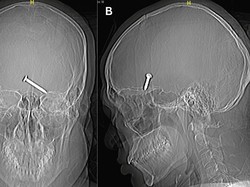

Horor! Begini Penampakan Paku Tembus ke Otak, Dokter Ungkap Kondisi Pasien

Seorang pria di Malaysia berusia 30 tahun lolos dari maut setelah paku menancap di otaknya dan melukai matanya.